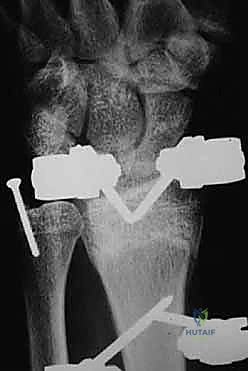

1. الأشعة السينية (X-rays): بوضعيات متعددة (أمامية خلفية، وجانبية دقيقة). الوضعية الجانبية الحقيقية (True Lateral) حاسمة لاكتشاف أي خلع جزئي في المفصل (DRUJ).

2. الأشعة المقطعية ثلاثية الأبعاد (3D CT Scan): تُستخدم في الكسور المفتتة أو كسور رأس الزند المفصلية المعقدة، حيث تعطي خريطة دقيقة للجراح قبل الدخول لغرفة العمليات.

ثانياً: العلاج الجراحي (Surgical Intervention)

1. عدم الاستقرار (Instability): إذا كان المفصل الزندي الكعبري البعيد (DRUJ) غير مستقر بعد تثبيت كسر الكعبرة.

2. الانزياح (Displacement): إذا كان الكسر في قاعدة الناتئ الإبري منزاحًا بأكثر من 2 ملم.

3. الكسور المفصلية: أي كسر يخل بتطابق السطح المفصلي لرأس الزند.

4. الكسور المفتتة: في الجزء الكردوسي التي تؤدي إلى قصر عظم الزند.

خطوات التدخل الجراحي الدقيق مع الأستاذ الدكتور محمد هطيف

تُعد جراحات المعصم والزند من الجراحات الدقيقة التي تتطلب مهارة عالية، وهو المجال الذي يتفوق فيه الأستاذ الدكتور محمد هطيف بفضل استخدامه لتقنيات الجراحة المجهرية (Microsurgery) والأدوات الجراحية ذات التقنية العالية.

يقوم الدكتور هطيف بدراسة الأشعة المقطعية ثلاثية الأبعاد بدقة، ويختار نوع وحجم الصفائح المعدنية (Plates) والمسامير (Screws) المناسبة لكل مريض بناءً على حجم العظم ونوع الكسر.